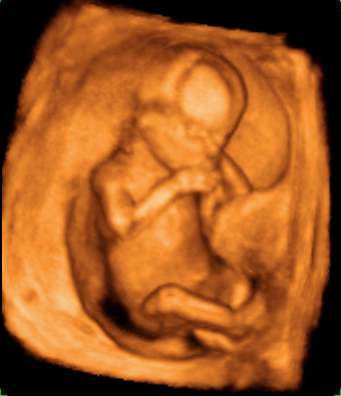

Ecografía 4D de la semana 12: Feto mirando "a la cámara"

Esta ecografía 4D muestra a un bebé de 12 semanas de gestación que se encuentra situado contra la pared del útero materno. El feto parece mirar varias veces hacia el ecógrafo y se tapa la cara con los brazos. Puede observarse con gran detalle la estructura ósea de la mano.

Ecografía en 4D de un feto de 12 semanas "mirando a la cámara"

A este niño de 12 semanas de gestación parece que le ha "pillado" el ecógrafo desprevenido y se quiere esconder. El bebé está contra la pared uterina: se da cuenta de que el ecografista le está "enfocando" y parece con si se quisiera esconder del público, como las estrellas de cine. Mira varias varias veces "a cámara", en una actitud sorprendente; se tapa la cara con los brazos. La mano se perfila perfectamente, así como muchas de sus estructuras óseas, mientras se esconde cara a la pared uterina.